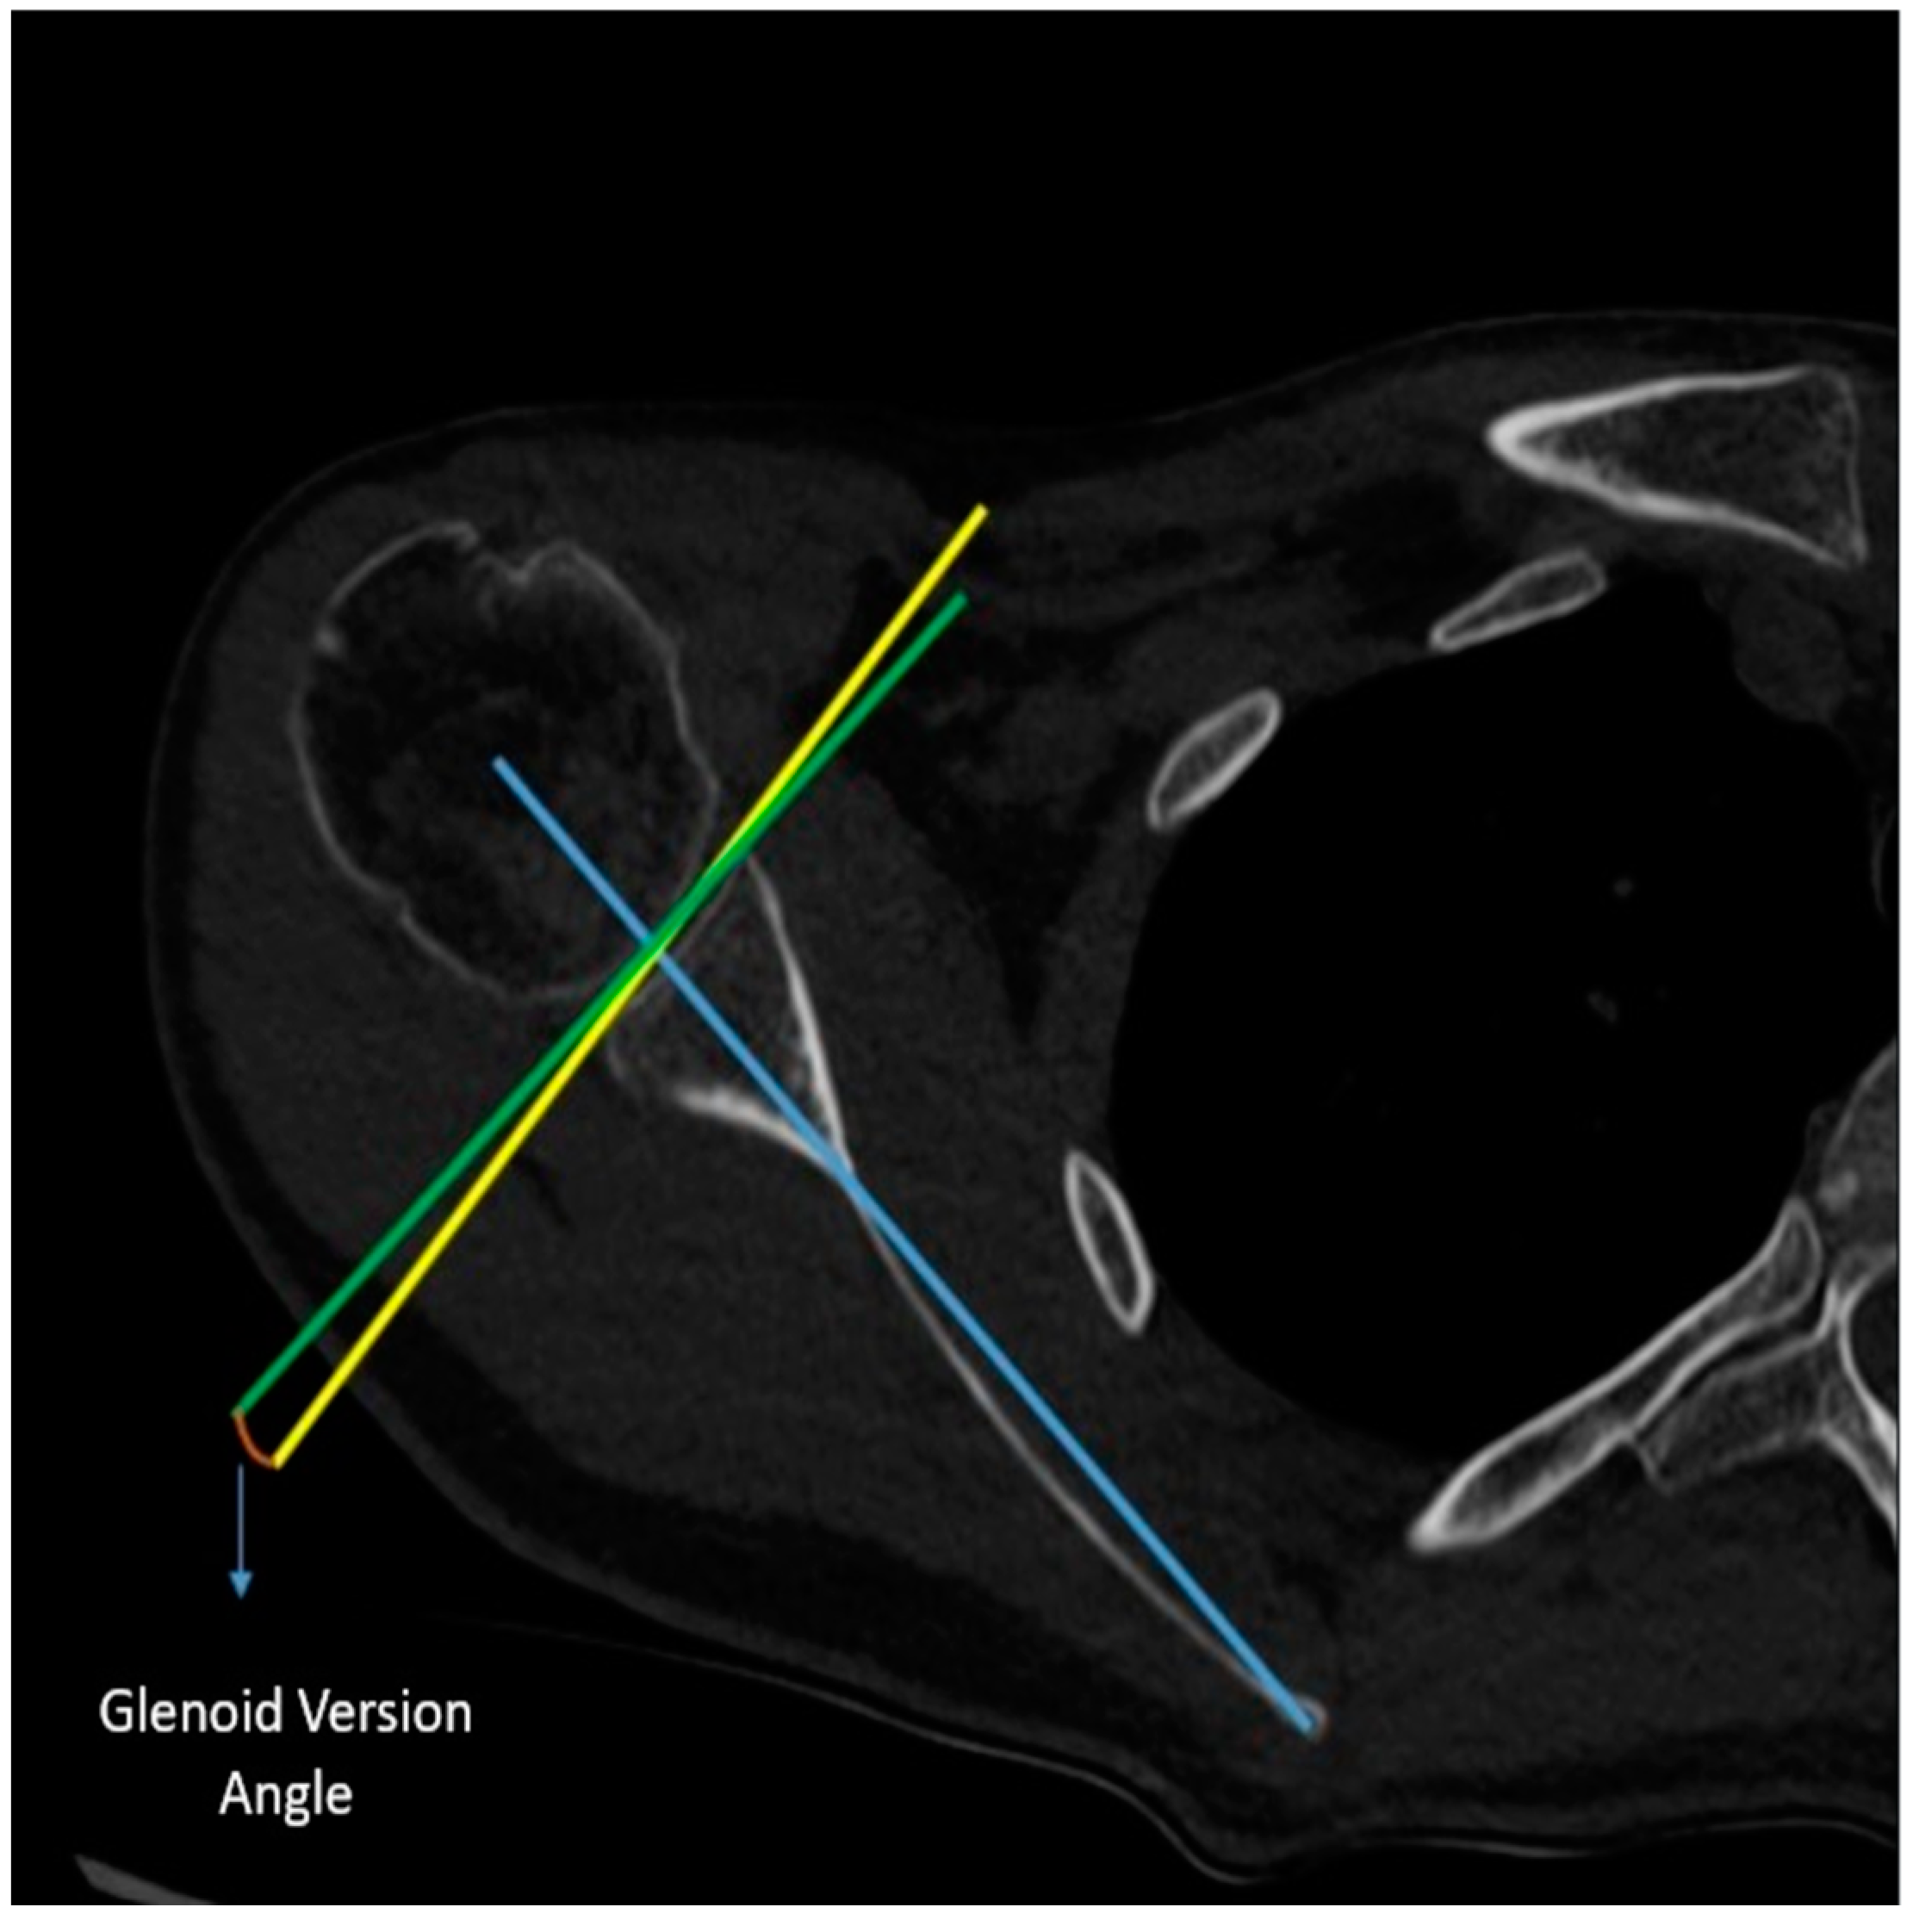

Measurement of Glenoid Version Angle: In the axial CT imaging, a line (referred to as the Friedman line) is drawn from the most medial border of the scapula to the center of the glenoid fossa. Subsequently, a line perpendicular to this scapular axis is drawn through the center of the glenoid. Following that, a line connecting the anterior and posterior rims of the glenoid is drawn. The angle formed between the line drawn perpendicular to the scapular axis and the line connecting the corners of the glenoid is assessed as the glenoid version angle (Figure 3).

Figure 3. Measurement of the glenoid version angle.